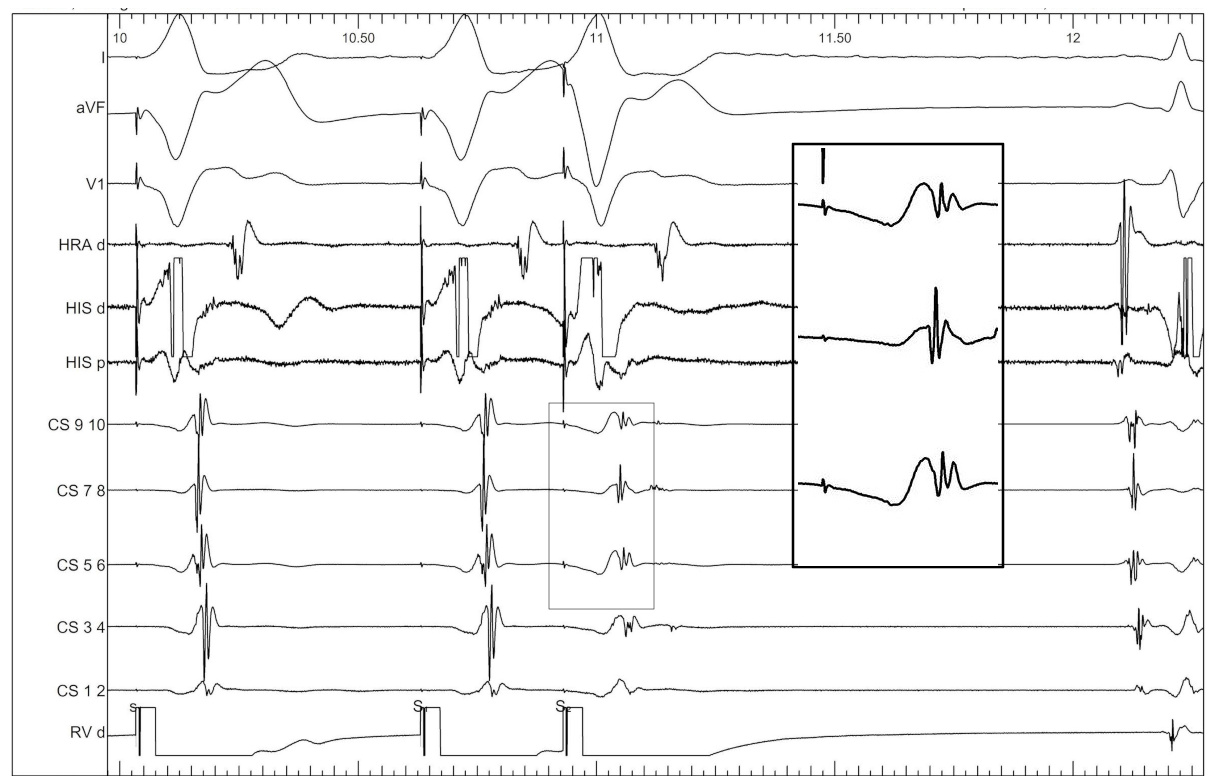

Ablate septal APs during tachycardia when possible

asap_ablation_tachy.jpg

Entrain when ablating free wall AP during tachycardia

entrain_ablate.jpg

Isthmus block

isthmus_block.jpg